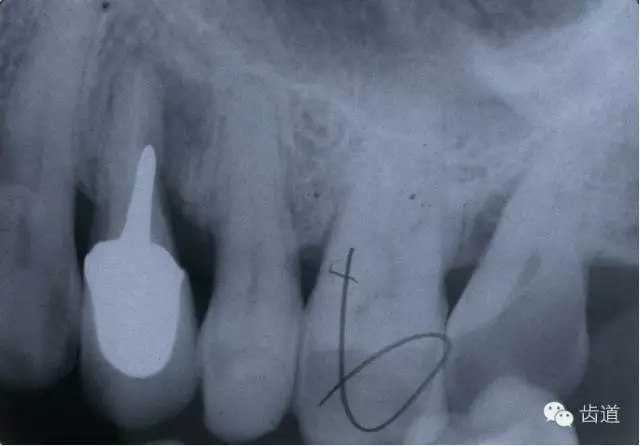

左上4鑄造樁側(cè)穿

(二)髓腔壁穿孔的診斷及處理

2.檢查:探診疼痛,且有鮮血;用根管長(zhǎng)度測(cè)量?jī)x探測(cè)可疑穿孔處,儀器發(fā)出報(bào)警聲;插診斷絲到可疑穿孔處拍X線片,可見(jiàn)診斷絲已超出髓腔范圍。